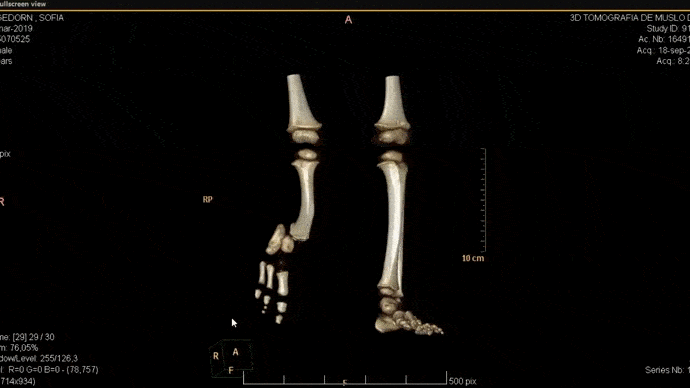

Ortopedia Infantil